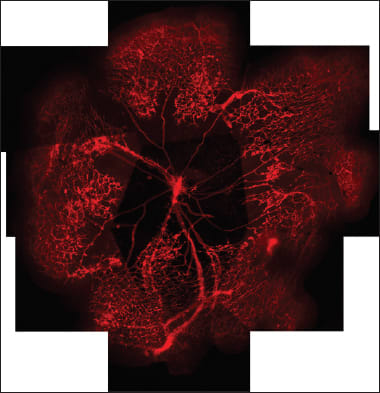

What evidence do we have to show that? It is very difficult to find animal models that show capillary dropout, but an effect on capillaries and capillary development can be demonstrated in the oxygen-induced retinopathy model commonly used in preclinical drug testing.5 In that model we do see the capillary loss, which is usually found reduced or eliminated by additional norrin (Figures 4–6). Similar capillary changes are seen in mouse pups treated with DKK, which blocks norrin Wnt signaling6 (Figure 7).

Figure 5. A montage of OIR models in the mouse with large areas of capillary dropout.